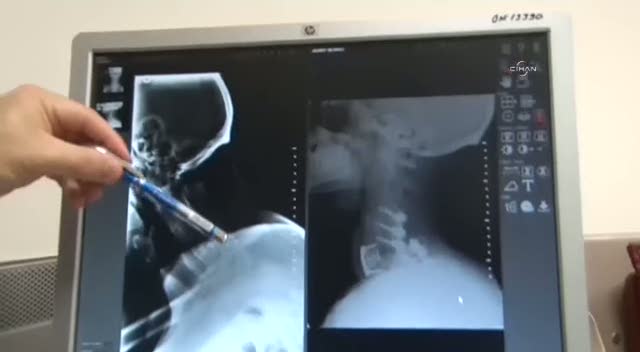

Sakarya'da omurga eğriliği ameliyatı olan hasta, operasyon sonrası serviste yatarken öksürünce boynunu kırdı. Hastanın eğik olan boynu da kırık sayesinde düzeltildi.